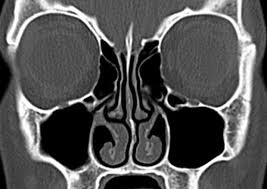

Symptoms Nasal Polyps Vs Normal : Minimally Invasive Sinus Surgery Provides Relief Of Nasal Polyps Where Other Surgeries Failed Cornerstone Ear Nose Throat - Find out about nasal polyps, which are painless soft growths inside your nose.. Nasal polyps are soft, painless growths inside the nasal passages. They usually occur in both the right and left nasal passages and can block the flow of air. Diagnosis of polyposis is based on the patient's complaints once discovered nasal polyps, treatment is possible both conservative and surgical methods. Symptoms are due to the size and location of the polyps and associated mucosal inflammation; They are painless and non cancerous growths.

Sometimes they grow large, though, and when. They are not dangerous, but they should still be treated for the patient's comfort at least if they do cause discomfort. Find out about nasal polyps, which are painless soft growths inside your nose. Nasal polyps (np) are noncancerous growths within the nose or sinuses. They often occur in the area where the upper sinuses drain into your nose (where your eyes, nose, and cheekbones polyps can grow large enough to block your nasal passages, resulting in chronic congestion.

Nasal Polyps Symptoms Treatment Philadelphia from www.bergerhenryent.com Nasal polyps (np) are noncancerous growths within the nose or sinuses. Nasal polyps are soft, painless growths inside the nasal passages. Larger ones can block normal drainage from the sinuses. The doctor may perform a biopsy of the polyp to ensure that it is not a cancer. Polyps in the nose are called nasal polyps. Learn about causes, risks, home remedies, and. They include nasal congestion and blockage, rhinorrhoea, posterior nasal drip. Normally these spaces are fairly open, but nasal polyps can grow large enough to.

In crswnp, nasal polyps are benign bilateral inflammatory outgrowths from the sinonasal mucosa. Diagnosed nasal polyps, treatment with modern methods that do the prognosis is more favorable. They include nasal congestion and blockage, rhinorrhoea, posterior nasal drip. They line the inside of your nose or your sinuses. Learn about causes, risks, home remedies, and. Symptoms are due to the size and location of the polyps and associated mucosal inflammation; They often occur in the area where the upper sinuses drain into your nose (where your eyes, nose, and cheekbones polyps can grow large enough to block your nasal passages, resulting in chronic congestion. Nasal obstruction is one of the main symptom of soft growths arising from mucous membrane of nose or paranasal sinus are referred as nasal polyps. They can make your nose feel stuffy, and can decrease your sense of smell. These polyps usually occur in both the right and left nasal passages and obstruct the flow of air. What is a nasal polyp? Symptoms of nasal polyps vary according to their size. A nasal polyp is a benign (noncancerous) tumor that grows from the lining of the nose or sinuses.

Some symptoms of crswnp such as nasal congestion the prevalence of nasal polyps in allergic rhinitis is not high and is similar to that in the normal population. You may also experience a sensation of constant mucus, which does not improve even when you blow your nose. Nasal polyps are caused by long standing allergies. Nasal polyps are small growths that can be found lining the inside of the nasal passage. These polyps vary in size, and they can grow singly or in clusters. Among its different varieties, simple mucus polyps are very common. Larger ones can block normal drainage from the sinuses. Symptoms are due to the size and location of the polyps and associated mucosal inflammation; Nasal obstruction is one of the main symptom of soft growths arising from mucous membrane of nose or paranasal sinus are referred as nasal polyps. Symptoms include trouble breathing through the nose, loss of smell, decreased taste, post nasal drip, and a runny nose. They often occur in the area where the upper sinuses drain into your nose (where your eyes, nose, and cheekbones polyps can grow large enough to block your nasal passages, resulting in chronic congestion. Nasal polyps are soft, painless growths inside the nasal passages. The doctor may perform a biopsy of the polyp to ensure that it is not a cancer.

Diagnosed nasal polyps, treatment with modern methods that do the prognosis is more favorable. However, they can be a big inconvenience and can interfere with the normal drainage. If the polyps are small and do not obstruct the nasal cavity, you may not have many symptoms. Find out about nasal polyps, which are painless soft growths inside your nose. However, if they grow larger or are in certain areas of the nose, they. Initially, sense of smell and taste may be muted, which can then be accompanied by partial or complete nasal obstruction. They can make your nose feel stuffy, and can decrease your sense of smell. Conservative treatment implies the elimination of. Doctors usually diagnose nasal polyps based on their characteristic appearance. Nasal polyps are benign (noncancerous) growths that may form inside nasal passages and sinuses — the spaces behind your nose and cheeks. What is a nasal polyp? What is a nasal polyp? If the polyps grow large enough then they can begin to cause some unwelcome symptoms.